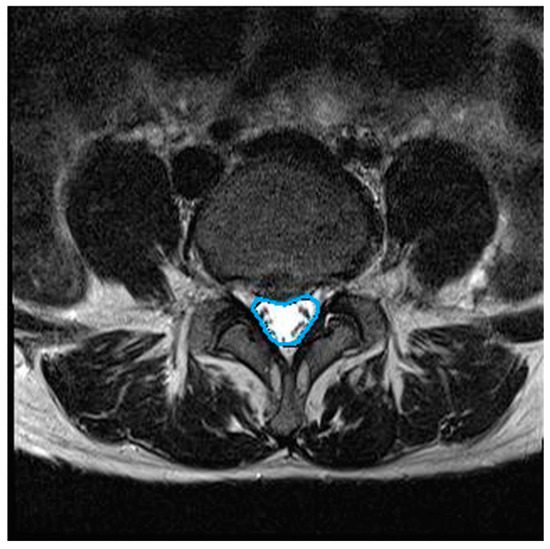

Background and Objectives: Lumbar traction is widely used as a non-operative treatment for lumbar intervertebral disc disease. The effect of traditional traction (TT) using linear-type traction devices remains controversial for various reasons, including technical limitations. Thus, the purpose of this study was to compare the effects of the newly developed lumbar lordotic curve-controlled traction (L-LCCT) and TT on functional changes in patients and morphological changes in the vertebral disc. Materials and Methods: A total of 40 patients with lumbar intervertebral disc disease at the L4/5 or L5/S1 level as confirmed by magnetic resonance imaging were recruited and divided into two groups (L-LCCT or TT). The comprehensive health status changes of the patients were recorded using pain and functional scores (the visual analogue scale, the Oswestry Disability Index, and the Roland–Morris Disability Questionnaire) and morphological changes (in the lumbar central canal area) before and after traction treatment. Results: Pain scores were significantly decreased after traction in both groups (p < 0.05). However, functional scores and morphological changes improved significantly after treatment in the L-LCCT group only (p < 0.05). Conclusions: We suggest that L-LCCT is a viable option for resolving the technical limitations of TT by maintaining the lumbar lordotic curve in patients with lumbar intervertebral disc disease. Full article

Figure 1